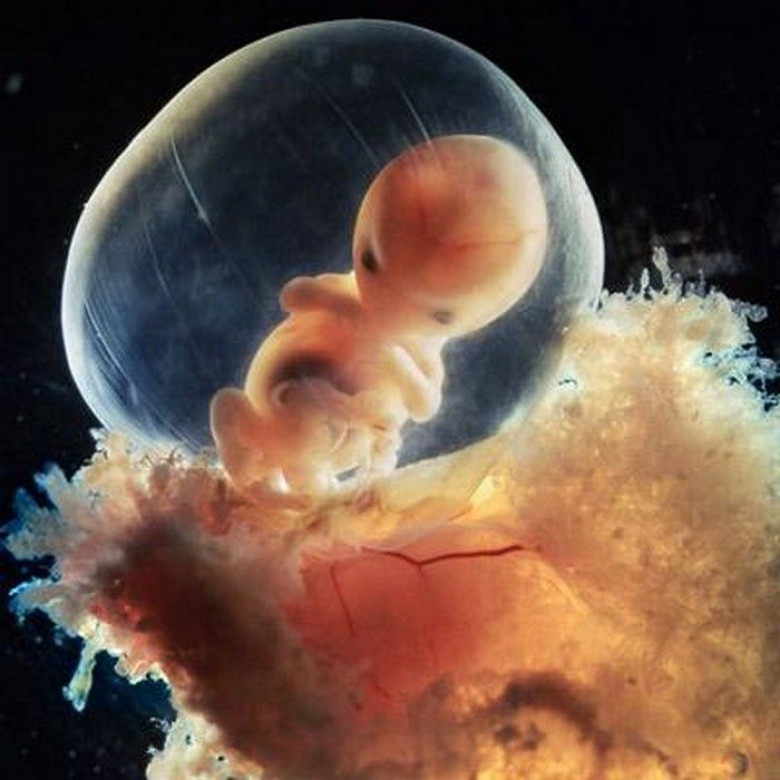

Сорок дней. Образовалась плацента.

Конец восьмой недели. Все мы когда-то были такими вот инопланетянами.